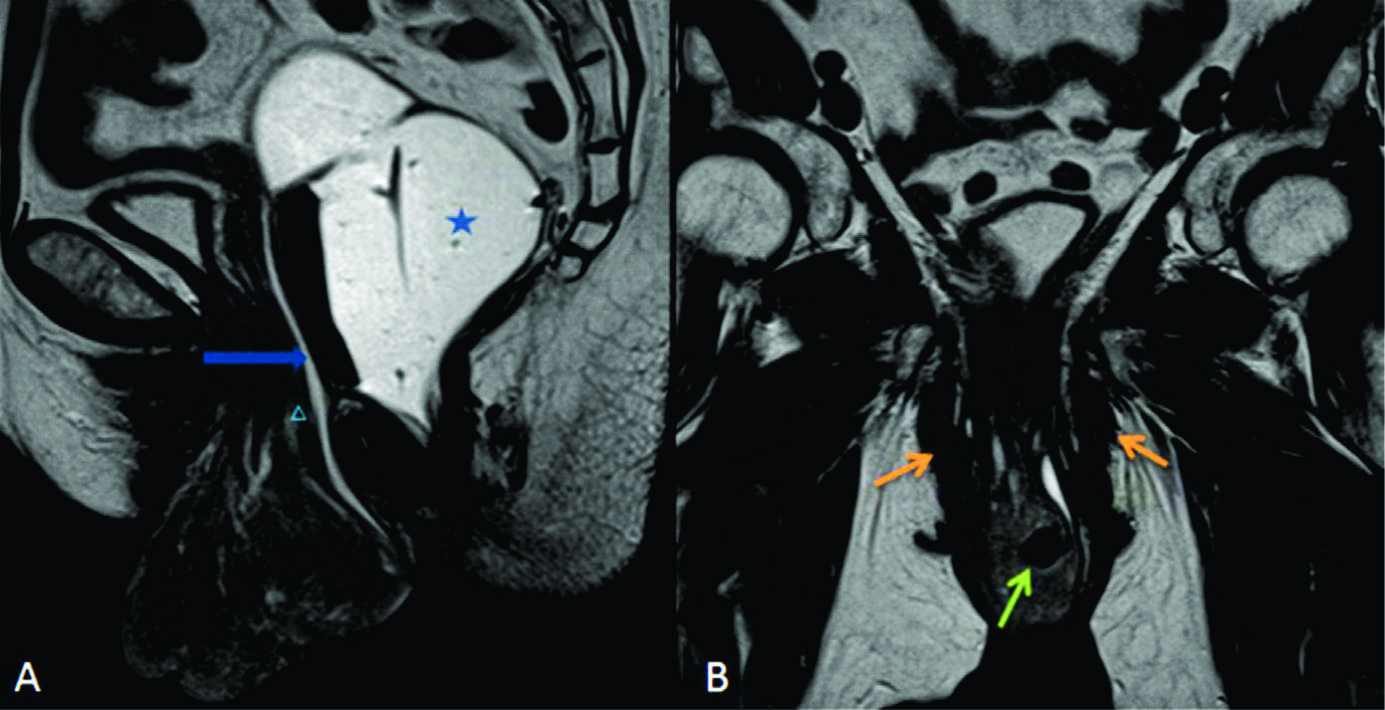

Figura 5

Uterocele.

Imágenes potenciadas en T2 de alta resolución en el plano A) sagital y B) coronal a nivel de la línea media de una mujer durante el reposo. Recto distendido con gel ecográfico tibio (estrella en A). Se observa prolapso de la cúpula vaginal (triangulo en A) y severo uterocele. Véase la herniación de grasa mesentérica (flecha azul en A) y la debilidad de las estructuras de soporte (flechas naranjas en B). Mioma uterino (flecha verde en B).